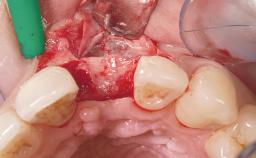

Immediate Placement of an Implant in a Maxillary Left Central Incisor Site

A 33-year-old female patient presented with an upper left central incisor that required extraction after a failed endodontic therapy. The tooth had been traumatized when the patient was a teenager and had undergone several endodontic treatments, including two apicectomy procedures. The patient was in good health and did not smoke. Clinical examination showed that the patient had a high lip line. In full smile, the gingival margins of the upper teeth were visible to the first molars. The gingival margins of central incisors 11 and 21 were only just showing. Examination of tooth 21 confirmed that the tooth was mobile and had hypererupted by 1 mm.

Soft Tissue Grafting Simultaneous

Placement Protocol Immediate implant placement

Tooth Site Maxillary incisor or canine

Socket Morphology Single-root socket

Socket Integrity Damage to one or more bone walls

Bone Volume Damage to one or more socket walls